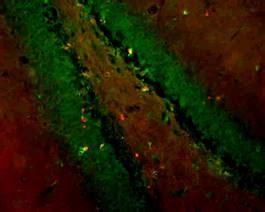

ER-PM Junctions on GABAergic Interneurons Are Organized by Neuregulin 2 ...